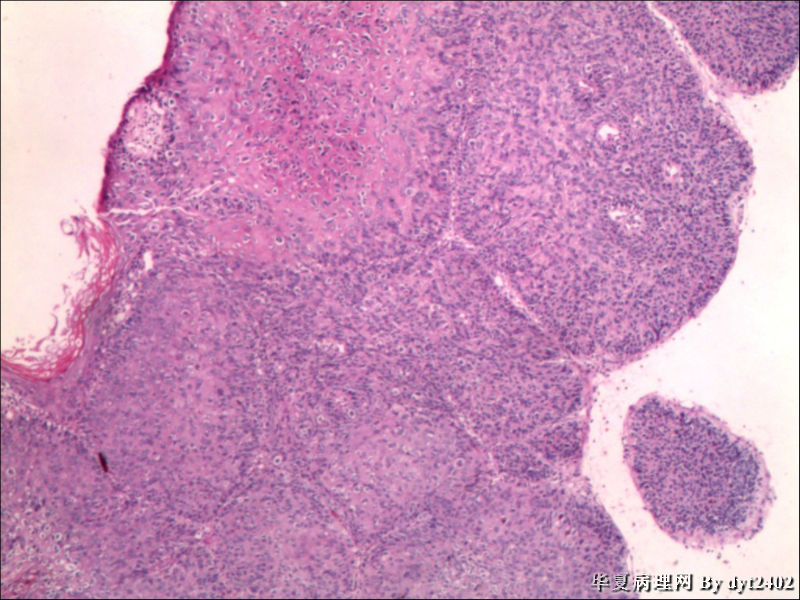

• 宫颈活检 其中一点较迷糊图3

图3

四点中三点是CIN iii,另一点怀疑有更重病变

这个病人是44岁,去年11月底阴道脱落细胞、TCT均见细胞异常,建议活检,病人犹豫,接着单位组织到外院体检时做阴道镜正常,后霉菌感染,此时宫颈未涂醋肉眼看还光滑,直至今年3月来做活检,事前做白带检查又见异常细胞,宫颈未涂醋见后上唇白上皮,涂醋酸后上下唇都有厚白上皮,镶嵌,夹活时上皮剥脱,未能夹到间质,阴道镜医生说至少有CIN III 到原位癌了。。镜下其中3点CIN III无疑,唯有9点处如6、7、11、14等所示结构,但我未见间质浸润,不能说是浸润癌,不知道有没基底细胞样鳞癌的可能,我发了个原位癌不除外深部有更重病变,。